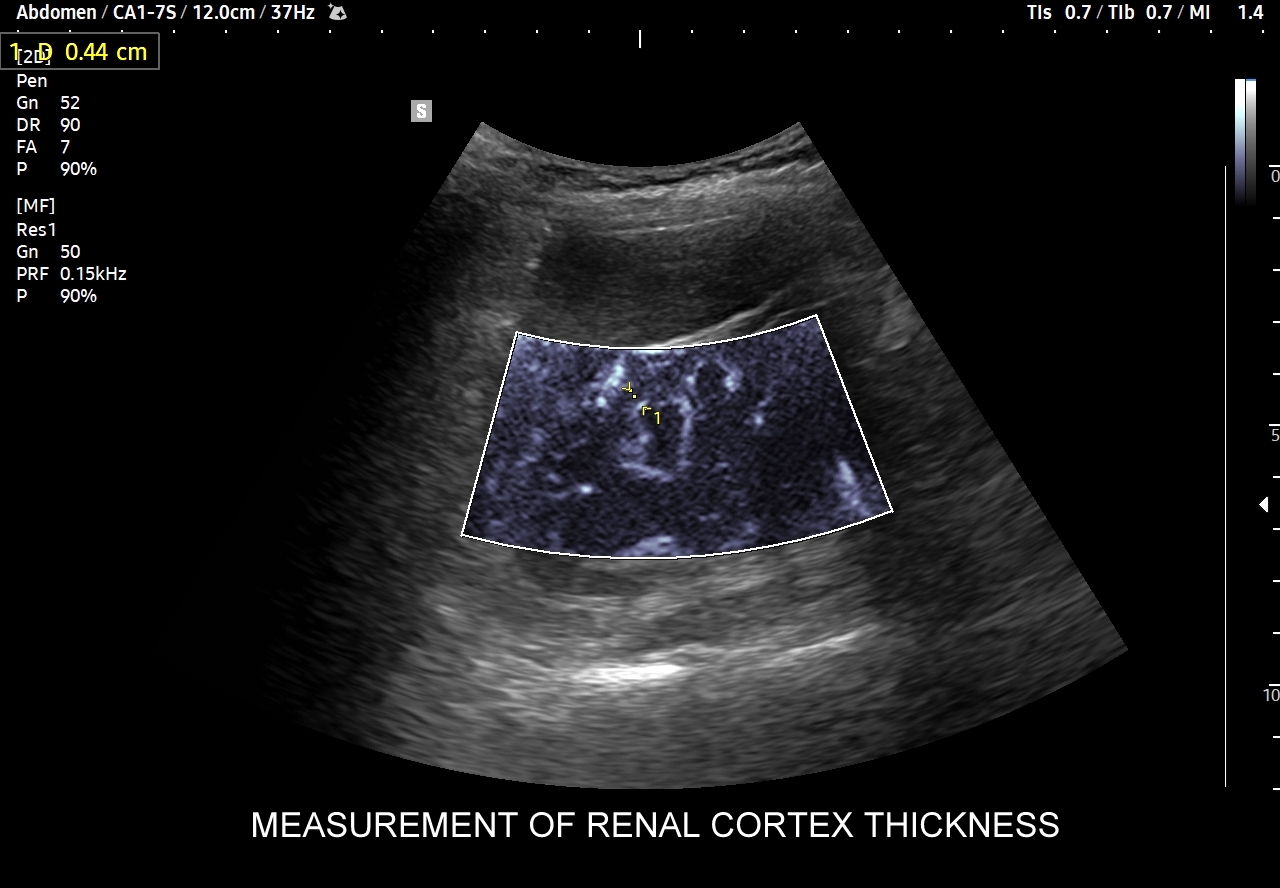

W badaniu USG ogniska endometriozy zwykle przyjmują formę hypoechogennych guzków i nieregularnych mas; mogą być niejednorodne echogenicznie i zawierać drobne obszary torbielowate; w trybie color-Doppler i MVI wykazują skąpe unaczynienie.

Na skanach w niniejszym artykule zaprezentowany jest przypadek endometriozy głębokiej w miednicy mniejszej z intraluminalnym nacieczeniem dystalnego odcinka moczowodu, jego całkowitą niedrożnością i wtórnym wodonerczem. Choroba w tak zaawansowanym stadium wykryta została przypadkowo w rutynowym przezbrzusznym badaniu USG jamy brzusznej. W ramach diagnostyki różnicowej przeprowadzone zostały badanie CT, MRI oraz ureterocystoskopia z pobraniem materiału do badania histopatologicznego, na podstawie którego postawiono rozpoznanie endometriozy.